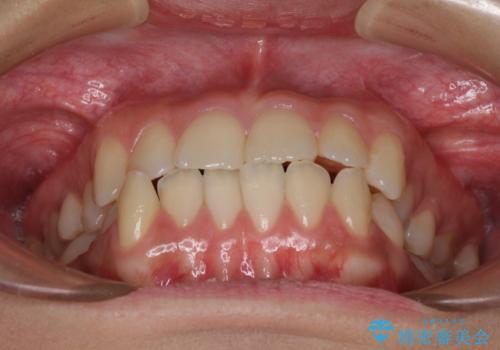

下顎歯列は上顎歯列内に収まるように並んでいますが、上顎骨の幅が狭いと、下顎臼歯が全体的に舌側に傾斜した歯列となってしまいます。

舌側に傾斜した歯列は奥歯に力の負担がかかりやすく、歯磨きがしにくいなどの問題があるため、上顎骨拡大により舌側傾斜を改善することが可能となります。